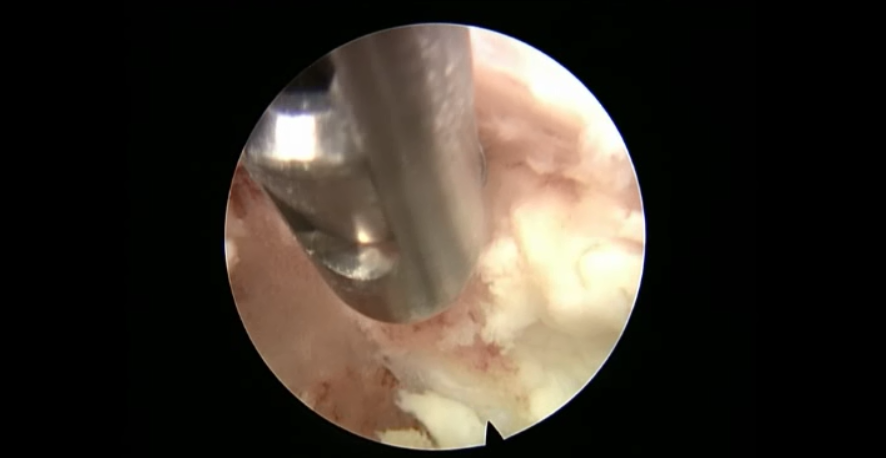

术中资料

点击以上图片,查看术中视频(超链接:http://res.orthonline.com.cn/video/case5---30.mp4)